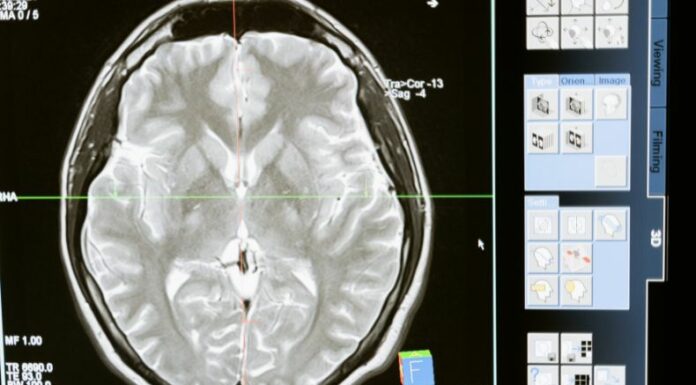

En el diagnóstico se realiza una evaluación médica por parte de un neurólogo, mediante los siguientes exámenes neurológicos:

- Imágenes por resonancia magnética (RMN).